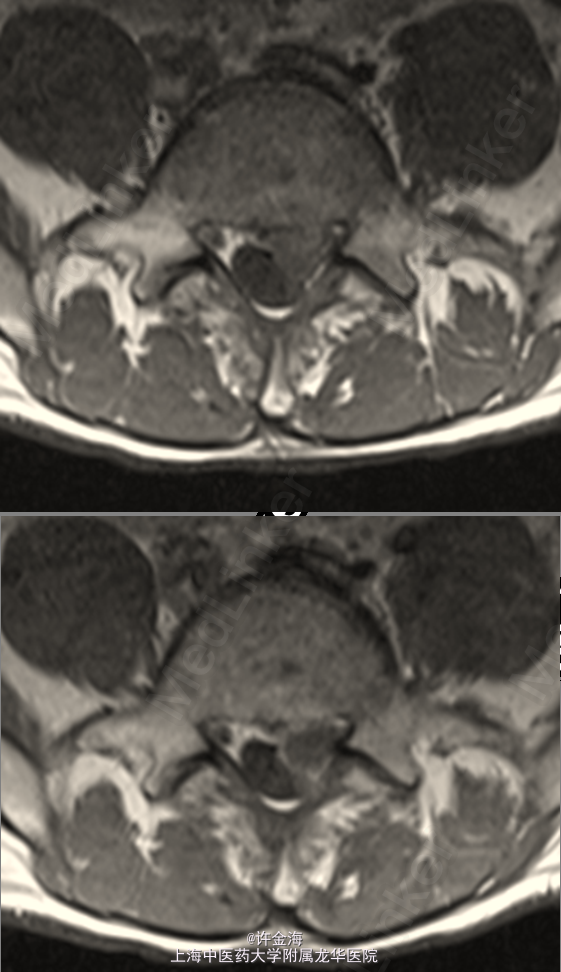

主诉:男,44岁。腰痛伴左下肢麻木、放射痛 一周

检查:L4/S1棘突、左侧棘旁压叩痛(+),左直腿抬高试验15°,加强(+),左4字试验(+),左下肢踇伸、跖屈IV级;浅感觉对称存在,双侧跟膝腱反射(+++),病理征(-)。

腰椎间盘突出症 术前:VAS腰6分,VAS腿8分,JOA12分 行全椎板切除减压,椎间盘摘除,cage融合,植骨内固定